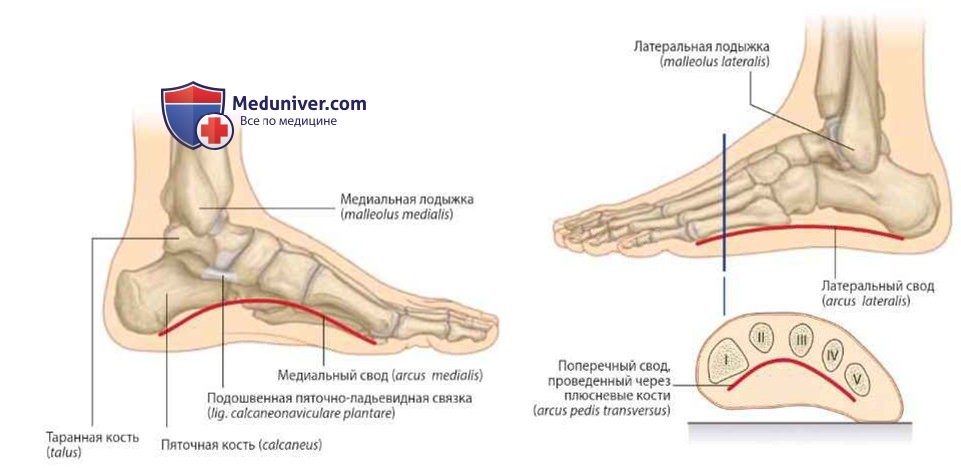

Анатомия: Блоки и сесамовидные кости в деталях